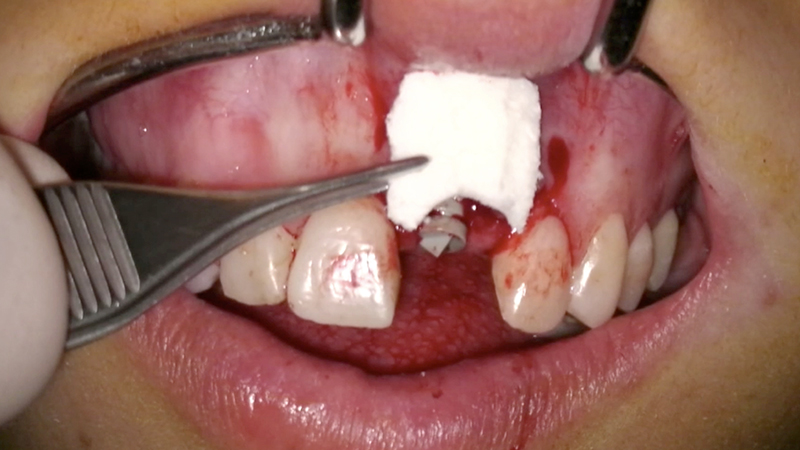

2. Rigenerazione ossea dell'alveolo 2.1 con Bio-oss e Muco-graft. In questa fase, il provvisorio fresato è stato cementato ai denti adiacenti con un filo metallico e composito. Dopo 5 mesi, ho ottenut il volume osseo necessario per poter posizionare l'impianto (Fig. 10a, Fig. 10b, Fig. 10c).

Rigenerazione ossea

Fig. 10b - Rigenerazione ossea.